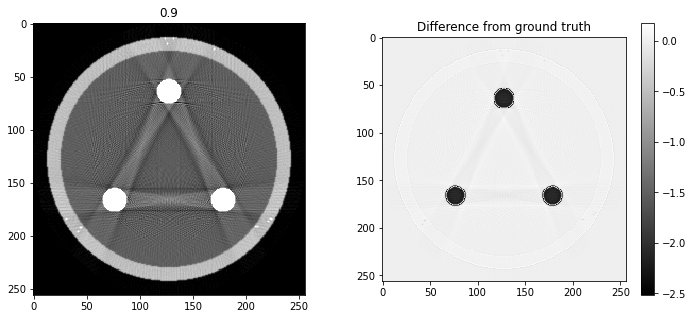

# Question 12

search = np.linspace(0,1,11)

for alpha in search:

rec = out+alpha*reproj

f,ax = plt.subplots(1,2,figsize=(12,5))

ax[0].imshow(rec,vmin=0,vmax=0.5)

ax[0].set_title(alpha)

im = ax[1].imshow(img[80]-rec)

f.colorbar(im,ax=ax[1])

ax[1].set_title('Difference from ground truth')

plt.show()